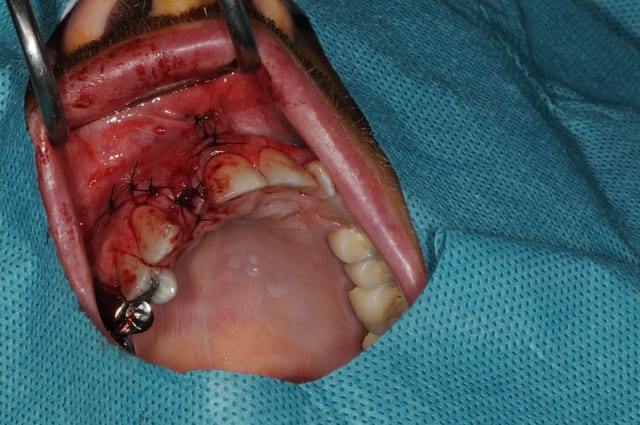

Salut, voila les photos de la chirurgie. rien d'extraordinaire , mais si certains ont des conseils, je suis preneur, j'ai la même chose à faire samedi matin

Pourriez vous me dire ce que vous utilisez pour éroder le mur palatin et éviter un axe trop vestibulaire?